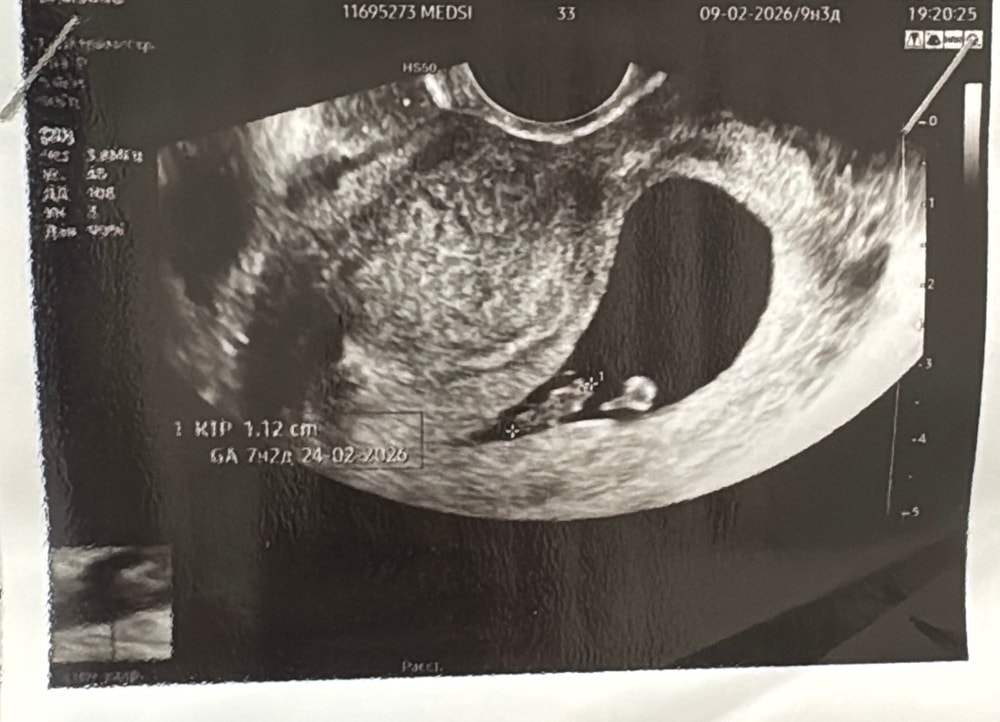

По данным скрининга сегодня срок 18+2.